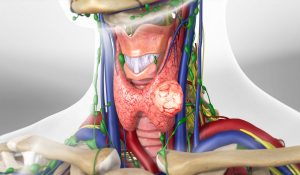

Операція Крайля (радикальна лімфодисекція шиї)

В організмі людини по ходу проходження лімфатичних судин розташовуються вузли, які являють собою справжні фільтри, де відбувається фільтрація і знешкодження чужорідних речовин.

Видалення щитоподібної залози в Івано-Франківську